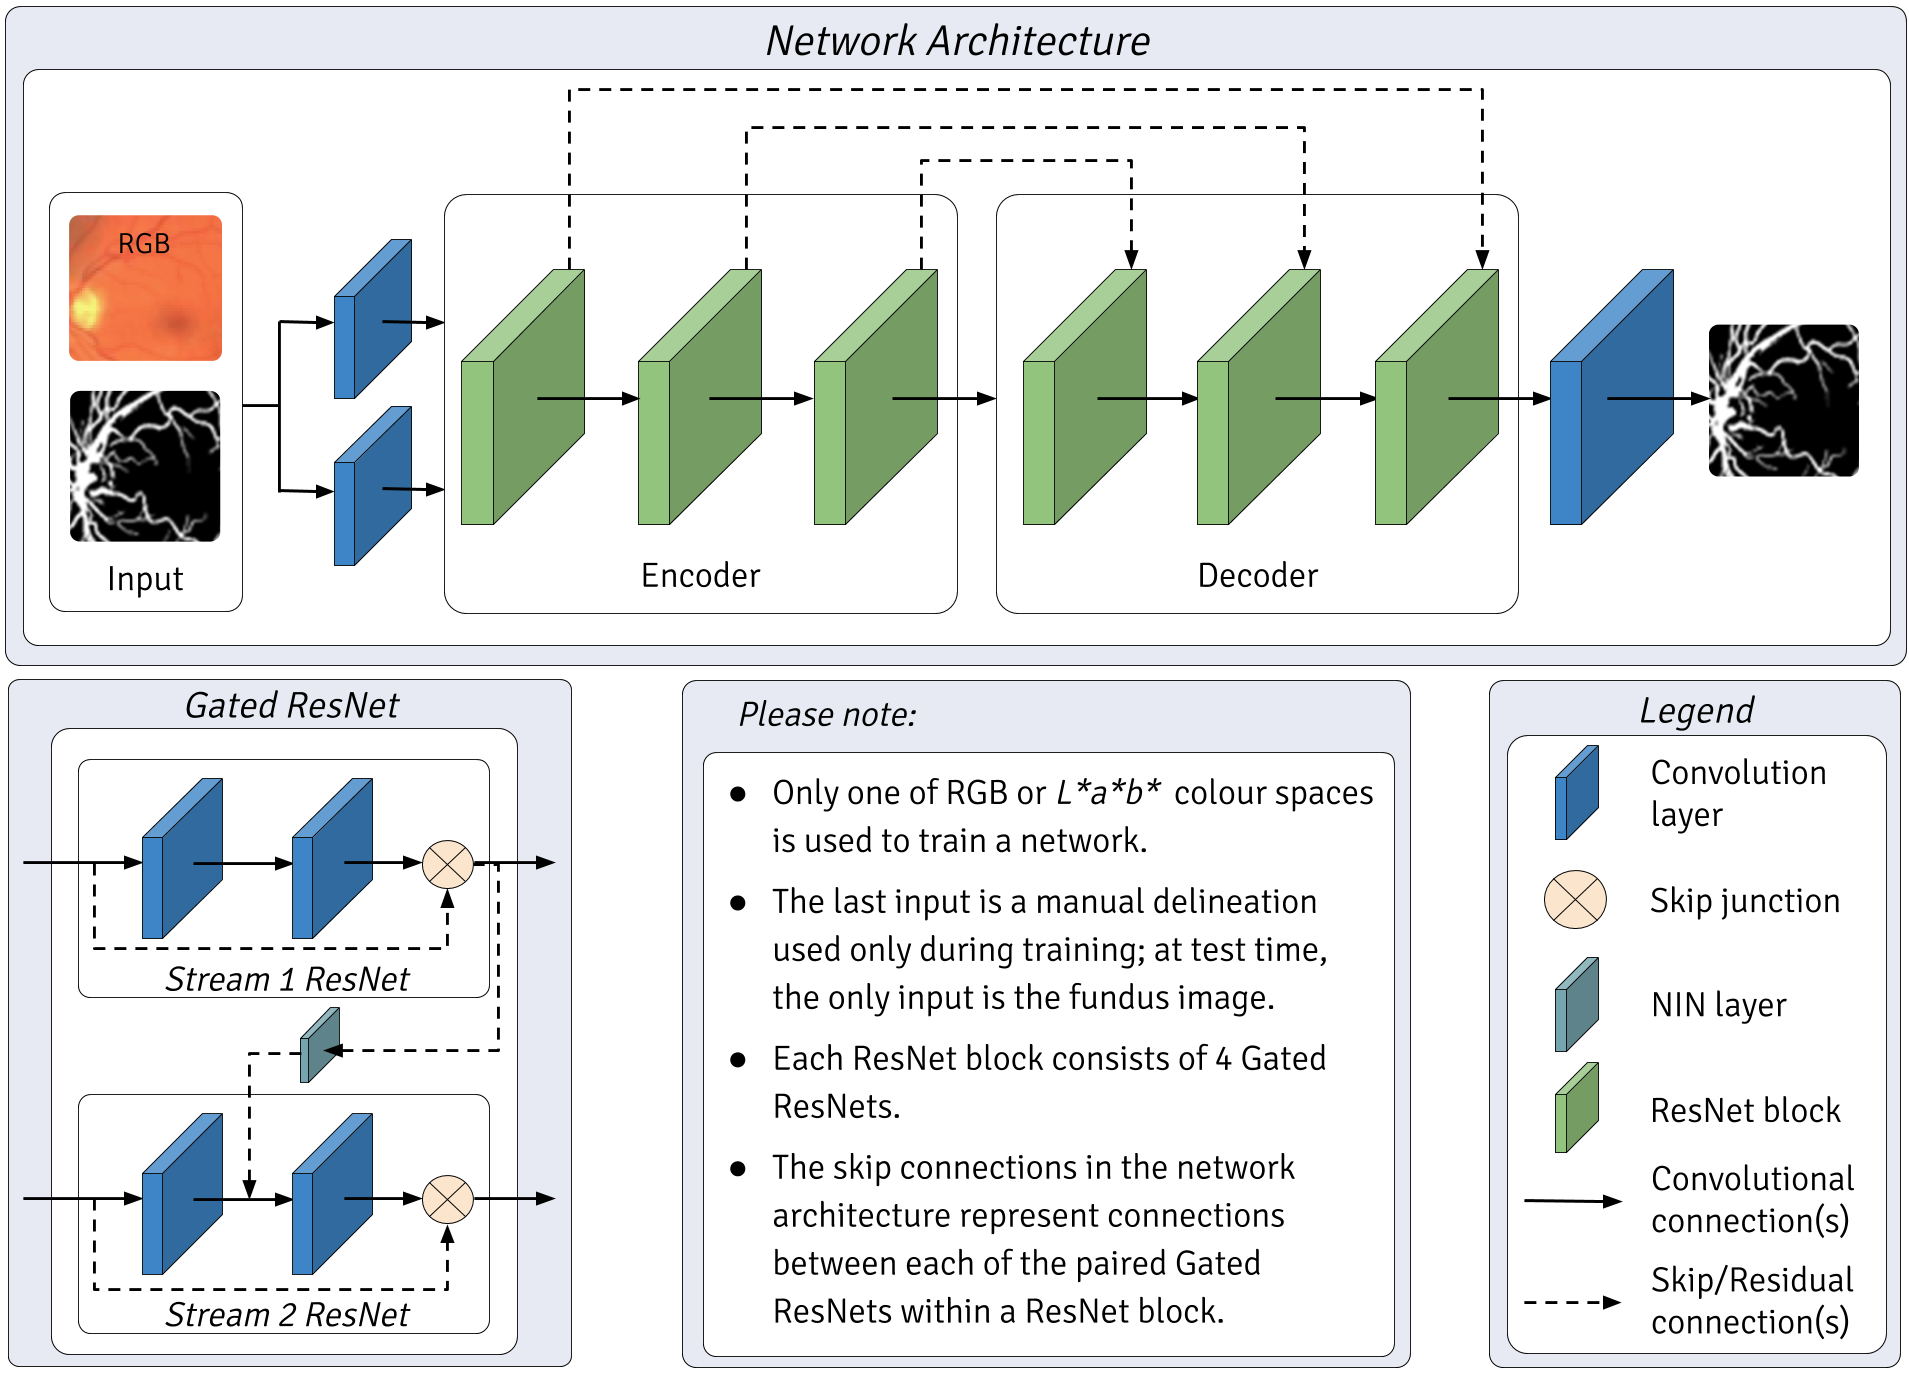

2.3 Network Architecture

PixelBNN is a fully-residual autoencoder with gated residual streams, each initialized by differing convolutional filters. It is based on UNET[28], PixelCNN [21] as well as various work on the use of skip connections and batch normalization within fully convolutional networks[29, 30, 31, 32]. It differs from prior work in the layer architecture, use of gated filter streams and regularization by batch normalization joint with dropout during training. While nuanced, the network further differentiates from many state-of-the-art architectures in its use of Adam optimization, layer activation by CReLU and use of downsampling in place of other multi-resolution strategies. The network makes extensive use of CReLU to reduce feature redundancy and negative information loss that would otherwise be incurred with the use of rectified linear units (ReLU). CReLU models have been shown to consistently outperform ReLU models of equivalent size while reducing the number of parameters by half, leading to significant gains in performance [33].

The architecture was influenced by the human vision system:

-

•

The use of two parallel input streams resembles bipolar cells in the retina, each stream possessing different yet potentially overlapping feature spaces initialized by different convolutional kernels.

-

•

The layer structure is based on that of the lateral geniculate nucleus, visual cortices (V1, V2) and medial temporal gyrus, whereby each is represented by an encoder-decoder pair of gated resnet blocks.

-

•

Final classification is executed by a convolutional layer which concatenates the outputs of the last gated resnet block, as the inferotemporal cortex is believed to do.

More detail on this subject is covered in prior work by the authors[17].

2.3.1 Downsampling without Information Loss

A popular method for facilitating multi-resolution generalizability with fully convolutional networks is the use of dilated convolutions within the model [21, 34]. Dilated convolutions can be computational expensive, as they continuously increase in size through the utilization of zero padding to prevent information loss. Downsampling is another a family of methods that sample features during strided convolution at one or more intermediate stages of a FCN, later fusing the samples during upsampling [29] and/or multi-level classifiers [31]. Such methods take advantage of striding to achieve similar processing improvements as dilated convolutions with increased computational efficiency, albeit with a loss in information. Variations in downsampling methods aim to compensate for this loss of information.

2.3.2 Proposed Method

Figure 2 illustrates the architecture of the proposed method. PixelBNN utilizes downsampling with a stride of 2, as well as long and short skip connections, resembling PixelCNN++ [22]. Implementing both long and short skip connections has been shown to prevent information loss and increase convergence speed [30], while mitigating losses in performance [35]. The method differs from PixelCNN++ in three ways. First, feature maps are implemented as with UNET[28] with a starting value of 16, doubling at each downsampling. Second, in the use of batch normalization after each downsampling and before dropout, rather than dropout alone. Third, it differs in its use of paired convolution layers on on continuous pixel space RGB images. Each gated ResNet block consists of 4 gated ResNets as shown in Figure 2. Each ResNet is made up of convolution layers with kernel size 3 and stride of 1. Stream 1 ResNet is gated with Stream 2 by a network in network (NIN) layer, which is a 1x1 convolutional layer like those found in Inception models[35].